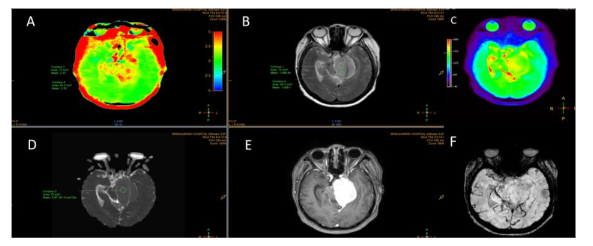

Figure 1: Meningioma, meningothelial variant (WHO grade I) (A): APT image shows increased APT signal of the right cavernous sinus in red color (B): S0APT image shows corresponding slightly increased APT signal area at the right cavernous mass. Area of red color consistent with artifact at skull base. (C): T2-weighted image and (D): contrast-enhanced T1-weighted image shows meningioma of right cavernous sinus.

Figure 4: Meningioma, meningothelial variant (WHO grade I): APT mean and APT max = 2.76, ADC value = 0.95 and ADC ratio = 1.22 (A) APT-weighted image shows increased APT signal at the left tentorial mass, ROIs were placed at the highest APT signal area corresponding to the S0 image (C) (B) T2-weighted image and (E) contrast-enhanced T1-weighted image show enhanced mass at the left tentorium in keeping with meningioma (D) ADC maps with ROIs placed at the meningioma (F) SWI shows no internal calcification or hemorrhage.